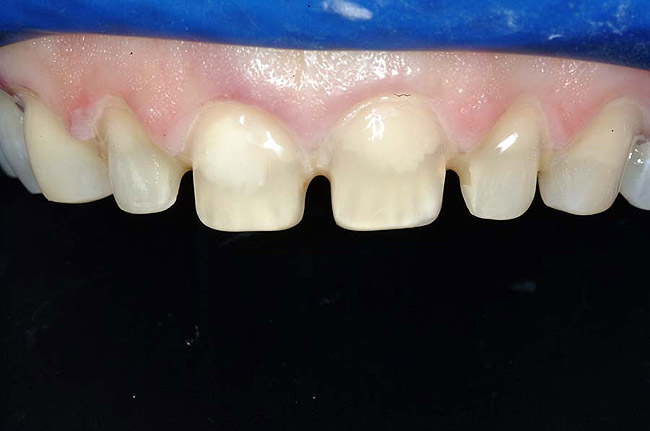

For example, before initiating the cementation process, preparations must be thoroughly cleansed (Figure 3), and adequate hemostasis and isolation should be ensured (Figure 4). Although newer generations of adhesives have been shown to be more tolerant of saliva contamination,7 proper isolation and hemostasis are still advisable because saliva and blood contamination cannegatively influence the bond strength of some bonding systems.8,9 Also,consider that resin cements are preferred for esthetic restorations, including porcelain laminate veneers.10,11 Successful use of these cements is dependent upon the incorporation of proper ceramic conditioning and tooth-surface treatment (ie, multiple-step total etch or self-etch adhesive)(Figure 8');" rem="#ip:figure5 through Figure 8">Figure 5 through Figure 8) to avoid incompatibility issues with the chosen cement and/or enhance the mechanical interlocking that occurs between the porcelain/resin-cement/tooth interfaces.10-13

<span id=Figure 4" border="0" height="199" hspace="0" src="/media/6771" title="Figure 4" width="300" />

Figure 4 To ensure adequate cervical access and promote hemostasis, a viscous, gingival retraction paste containing aluminum chloride (Expasyl™, Kerr Corporation) was placed in the sulci surrounding the preparations.